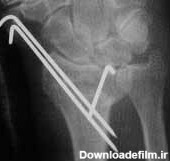

عکس پین مچ دست

تجهیزات تثبیت کننده ارتوپدی در درمان بسیاری از شکستگی ها و جراحی های ترمیمی کاربرد وسیعی دارند. بسیاری از موارد شکستگی های همراه با جابجایی استخوان با عمل جراحی درمان می شوند و در اغلب آنها از تجهیزات تثبیت کننده (ایمپلنت) داخلی، خارجی و یا داخل کانال استخوانی به منظور ثابت کردن و تنظیم جایگاه …